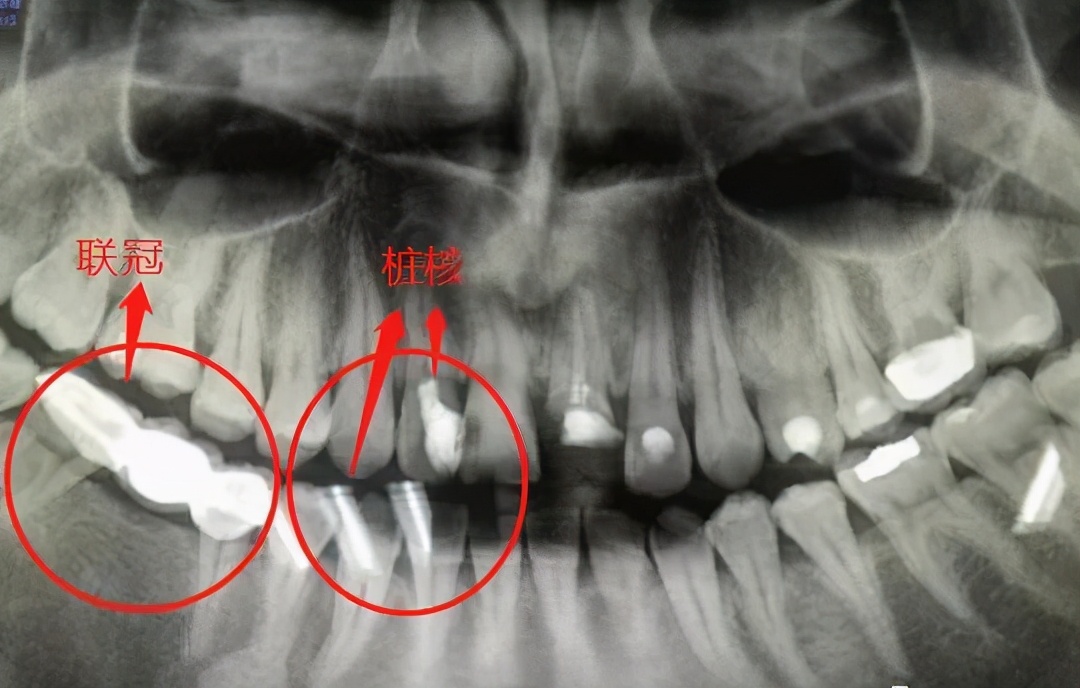

如果牙龈中的根足够长,通常可以进行核后冠。

由于只剩很少的牙齿组织,为了更好地固定牙齿,牙医会将牙桩插入根管中,在行业中我们称之为“牙桩”。

有些牙根短,如果单独修理,可能无法达到预期的效果。

这时,我们还可以将其与相邻的牙齿一起修复,以形成结合的牙冠,以增加牙齿的固位力和支撑力。

牙齿残根不疼就没事,别管它?!#雅悦齿科#

有些牙根太短,以至于即使使用后核冠也无法保存,因此医生会考虑使用覆盖义齿进行修复。